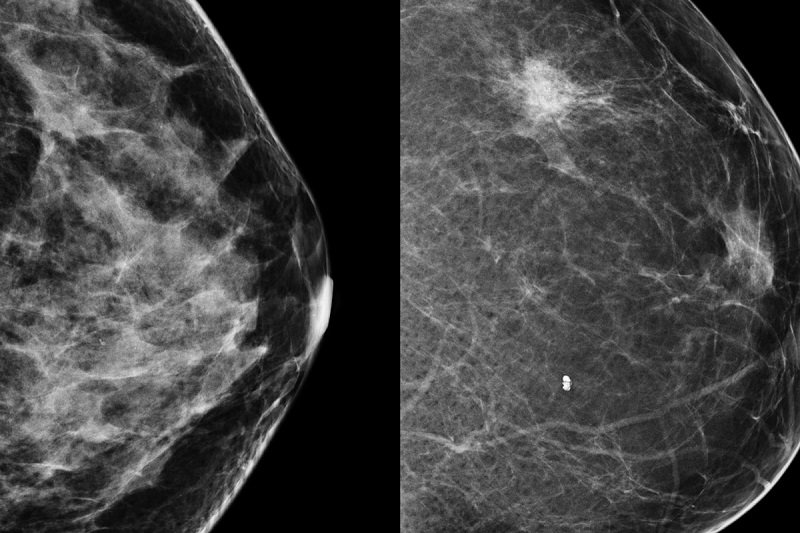

Профилактика рака молочных желез

Не зря же врачи по всему миру настоятельно рекомендуют каждой женщине регулярно обследоваться у гинеколога и маммолога. Простая профилактика позволяет отловить болезнь как можно раньше, а на начальных стадиях большинство видов рака сегодня абсолютно излечимы.

Не секрет, что лет 20–30 лет назад при выявлении рака и удалении молочных желез отечественные врачи тоже вырезали яичники, однако с тех пор диагностика и лечение шагнули далеко вперед. Каждой женщине стоит понять, что сегодня рак диагностируется легко и так же легко излечивается на ранних стадиях. Главное — это должная профилактика и ответственное отношение к собственному здоровью.

Благодаря раннему выявлению патологии, лечение рака молочной железы ведет к стойкому излечению. Среди женщин, проходящих регулярные профилактические осмотры у маммолога, в том числе и самообследование, летальный исход случается на 30–50 % реже, чем у женщин, которые профилактическими осмотрами пренебрегают.

«Я бы рекомендовал женщинам после 35 лет посещать маммолога раз в полгода. Эти специалисты раньше были экзотикой, а сегодня они вполне доступны и имеют на вооружении всё необходимое диагностическое оборудование», — рассказывает хирург-онколог Александр Дорофеев. И мы согласны с ним на все сто!